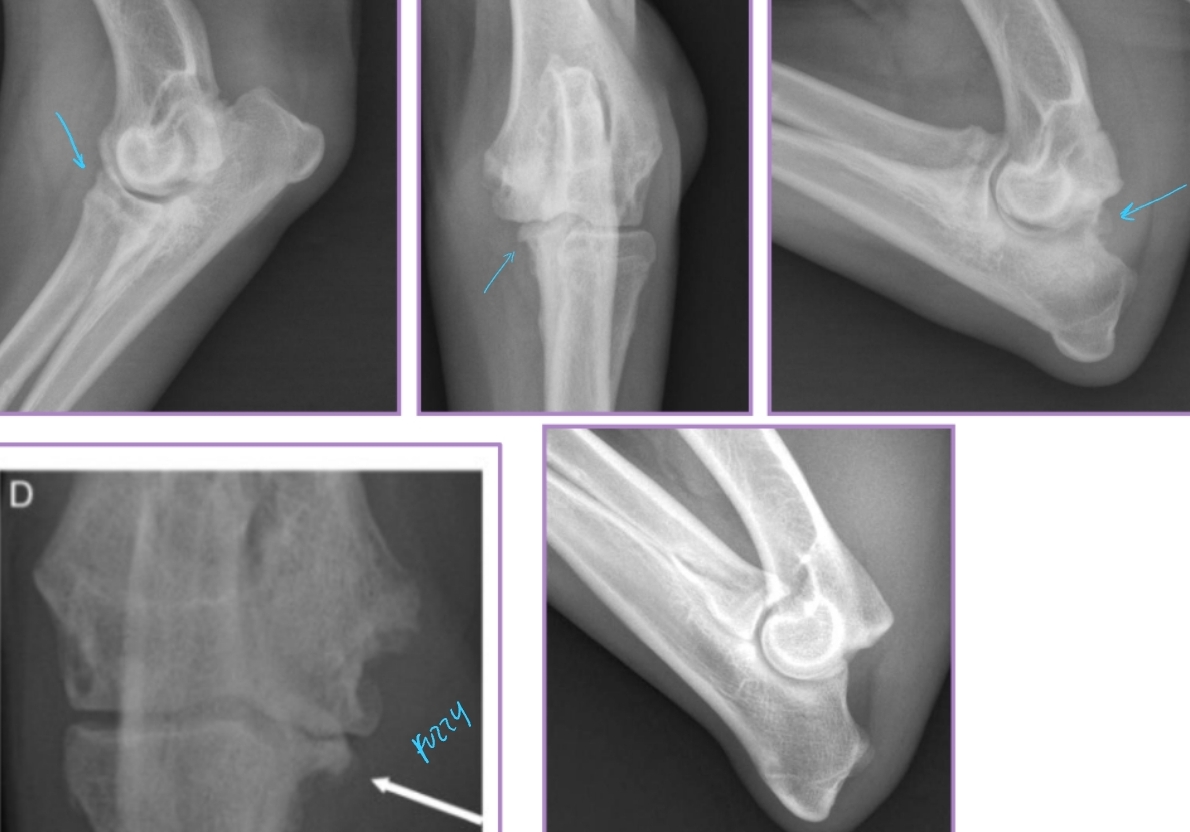

Elbow Dysplasia Clinical Presentation

Et: Genetics + environ factors

Ununited anconeal process, medial compartment disease, medial coronoid disease, OC, OCD, Elbow incongruity

Sig: Young >>> older, large breeds, rapidly growing dogs

Cs: lameness

#1 cause of forelimb lameness

Medial Compartment and Coronoid Disease

Dt: Lateral, AP, flexed, Crlat-oblique

Rads: Osteophytes(back of elbow), Effusion, Subtrochlear sclerosis, Joint incongruity

Ununited Anconeal Process

Et: Anconeal process of ulna fails to unite with proximal ulnar metaphysis

Failure of endochondral ossification, Joint incongruity

Hereditary, environmental, hormonal factors

Sig: Large breeds, GSD, Male > female, 5-12 months

Dt: Radiographs FLEXED lateral!

Osteophytes, Effusion, Anconeal process fragment, Joint incongruity

Elbow Incongruity

Et: Asynchronous growth of radius and ulna

Dt: radiographs